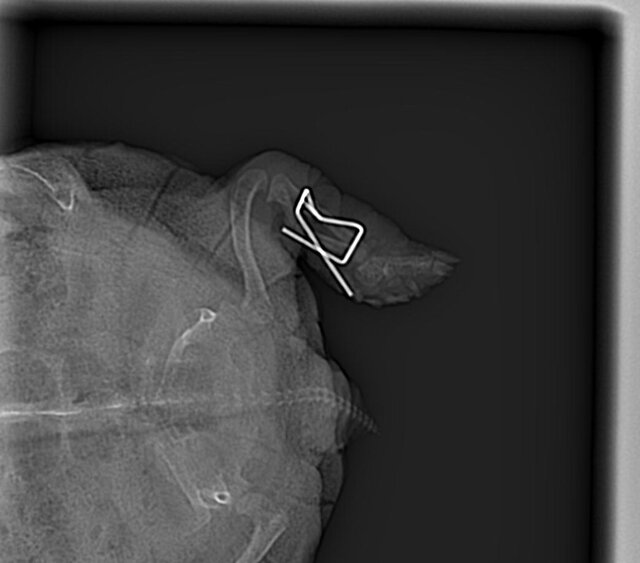

Решили таки сделать остеосинтез,ибо перелом застарелый и с простой фиксацией шансов ещё меньше.Тоже конечно хорошего мало.Лапа зафиксирована,но зафиксирована "внутрь"(фотку приложил).Вся процедура вместе с наркозом длилась пять часов,сейчас бедная лежит,отходит от наркоза.

Шансы на спасение ноги 50/50,а учитывая пожизненное "везение" Дуси - чаша клонится в печальную сторону.Но надежды не теряем,будем биться до конца.

Дуся остеосинтез    27.04.2024.jpg

20240627_195654.jpg